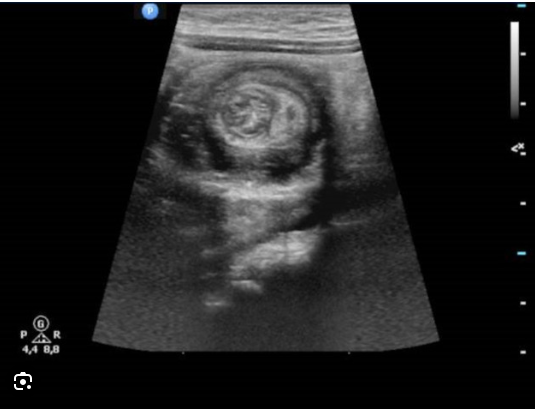

Intussuscepção intestinal

Clínica, diagnóstico e tratamento

• Invaginação proximal do intestino em segmento adjacente distal atráves da válvula ileocecal

• Idiopático ou lesão anatômica (Divertículo de Meckel, tumores,linfoma)

Quadro Clínico

• Ocorre em crianças pequenas

• Choro intenso

• Fezes sanguinolentas (geleia de framboesa)

• Dor abdominal intermitente

• Vômitos

Diagnóstico:

• USG ABDOMINAL

• Raio-X

• Enema Baritado

Tratamento:

• Redução por enema

• Cirurgia (se enma refratário, choque, peritonite)

Sinal em alvo